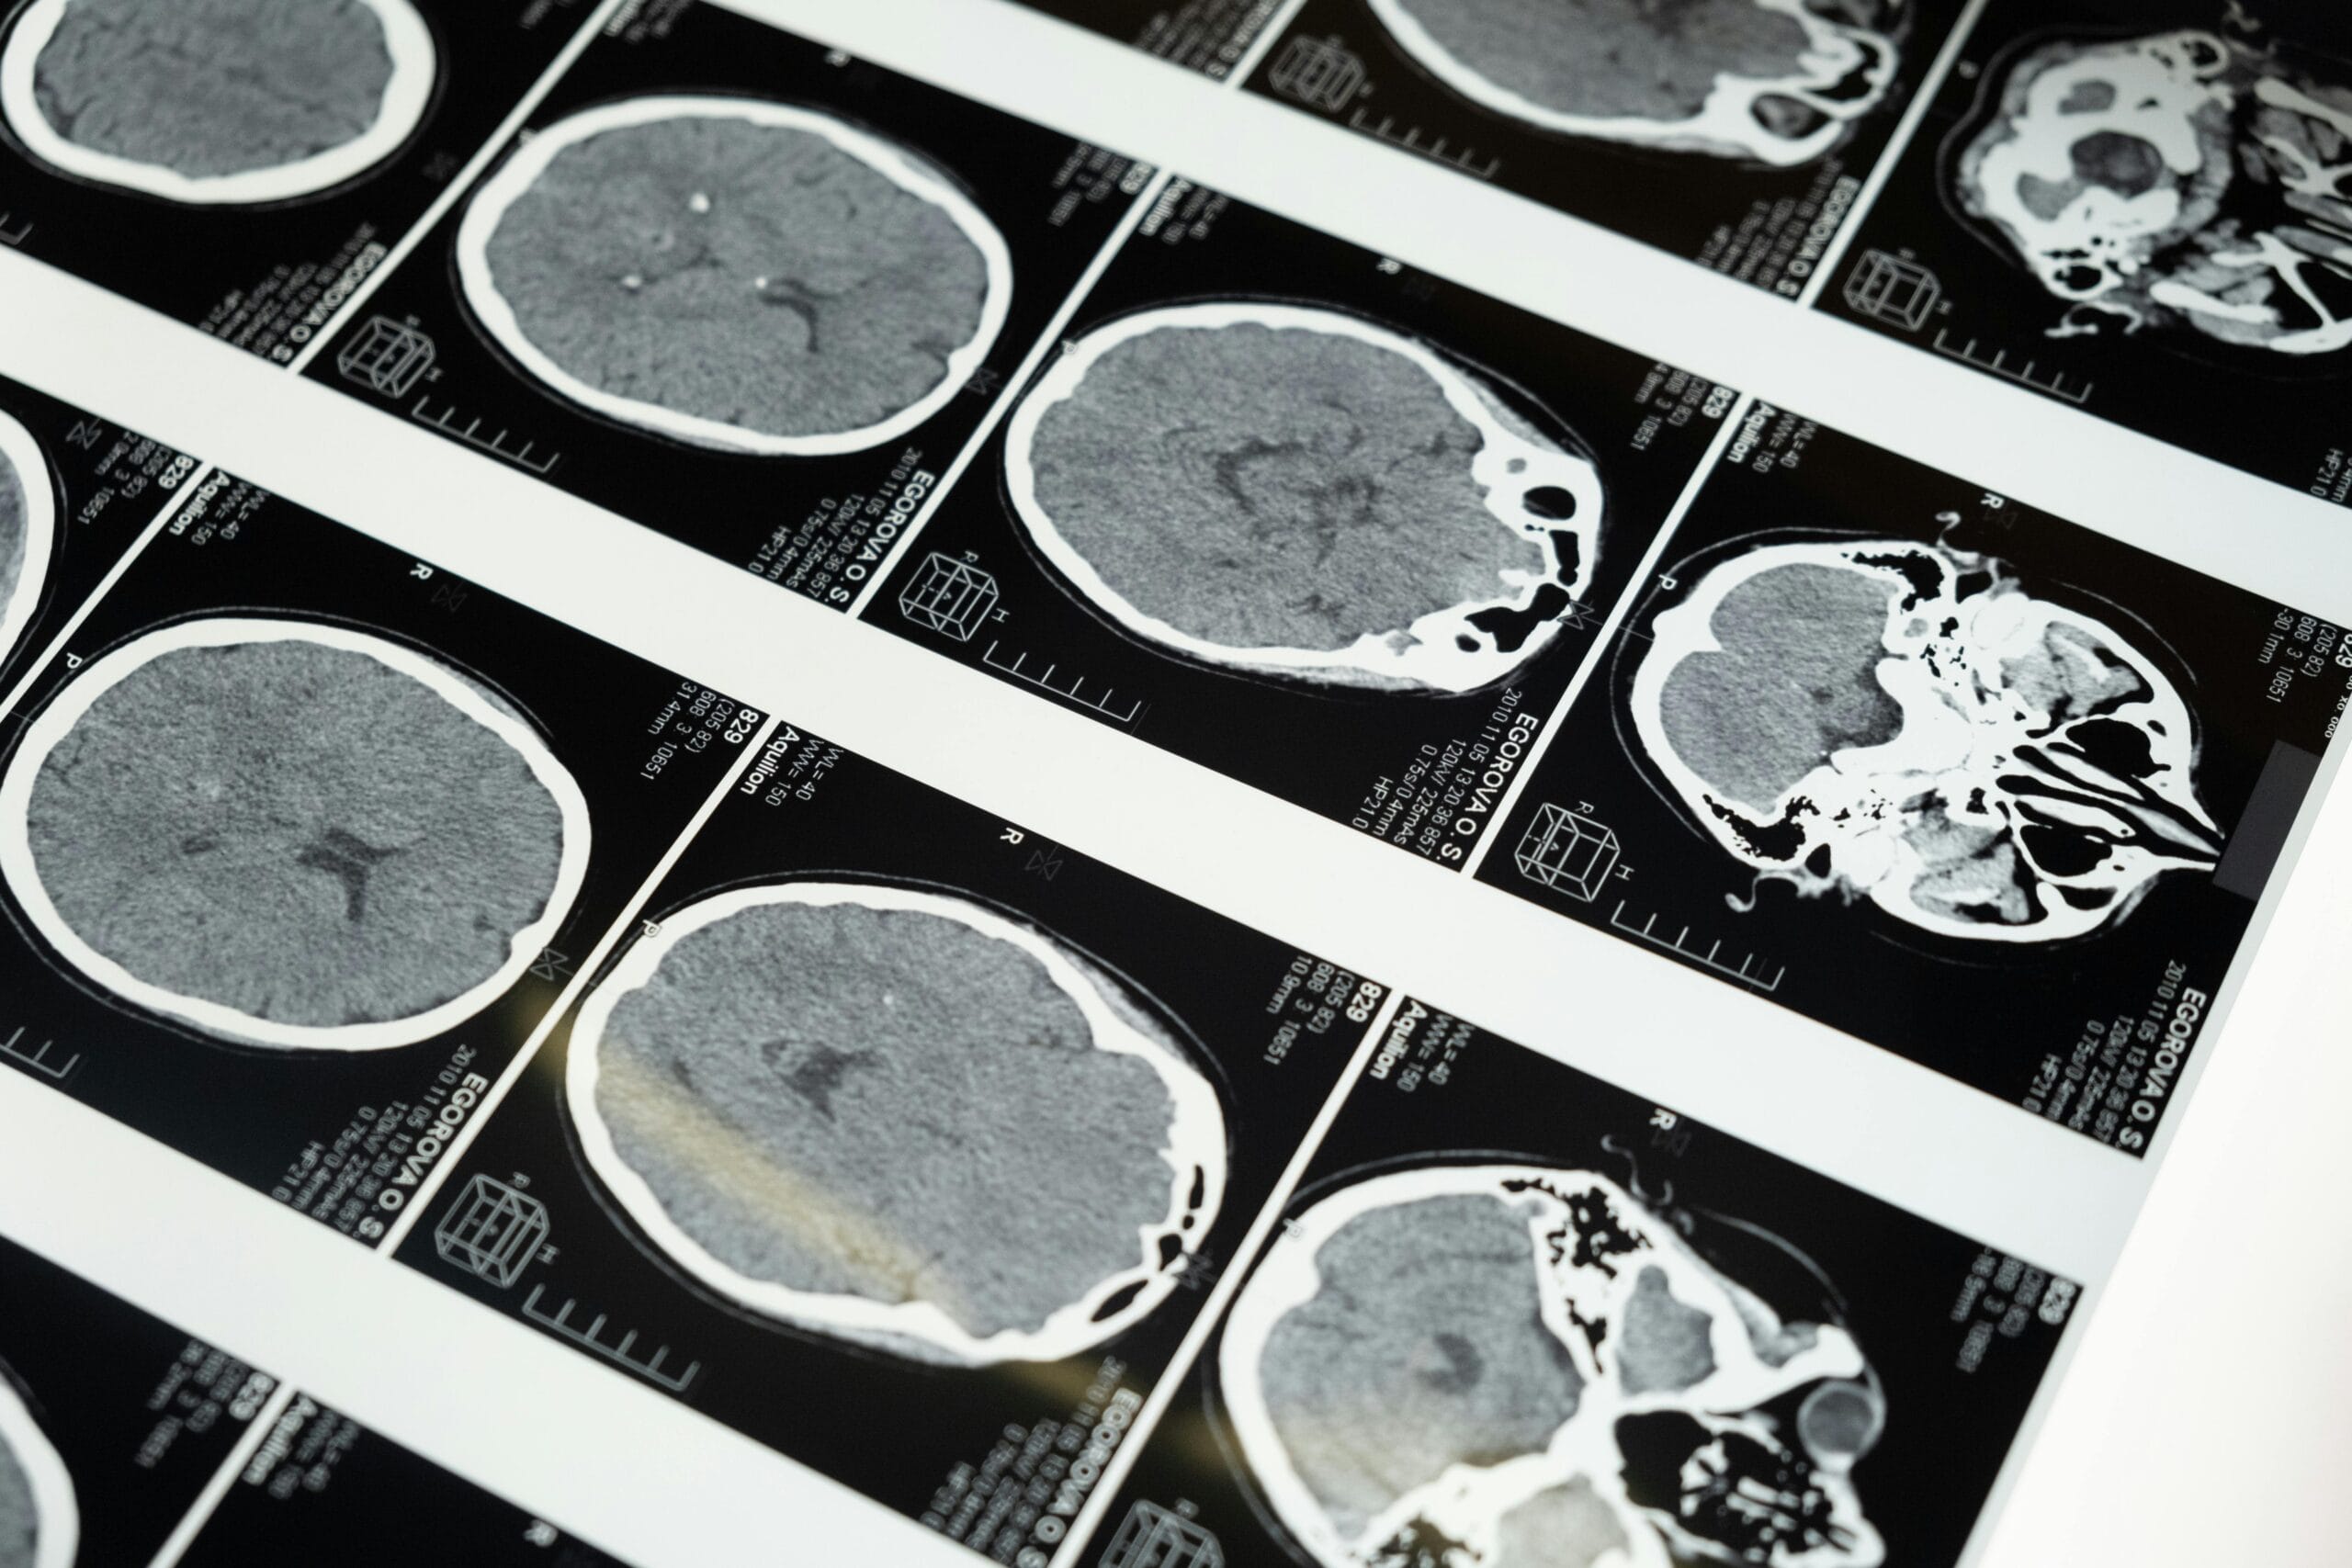

In the clinic, you often meet fascinating people and hear interesting pain stories. Phil is one example. A highly charismatic and talented amateur jockey, he came off a bicycle at great speed and hit a tree. He fractured his skull, sternum and sustained a complex spinal fracture, which was operated on shortly after the accident. He also has a bruised heart, spleen and other organs. He recalls;

“I thought I’d just got a cut to my head and pulled the muscles in my back. It was only really after the CT scan when they diagnosed me with the fractures that the pain and shock really kicked in.”

Much like our second scenario earlier, he was benefiting from stress-induced hypoalgesia until the moment he realised the extent of the damage. His recovery was outstanding, partly because of his confidence in his recovery, continual determination and lack of concern surrounding the injury. A few months later he was in the gym lifting heavy weights and is now back riding bikes and horses.